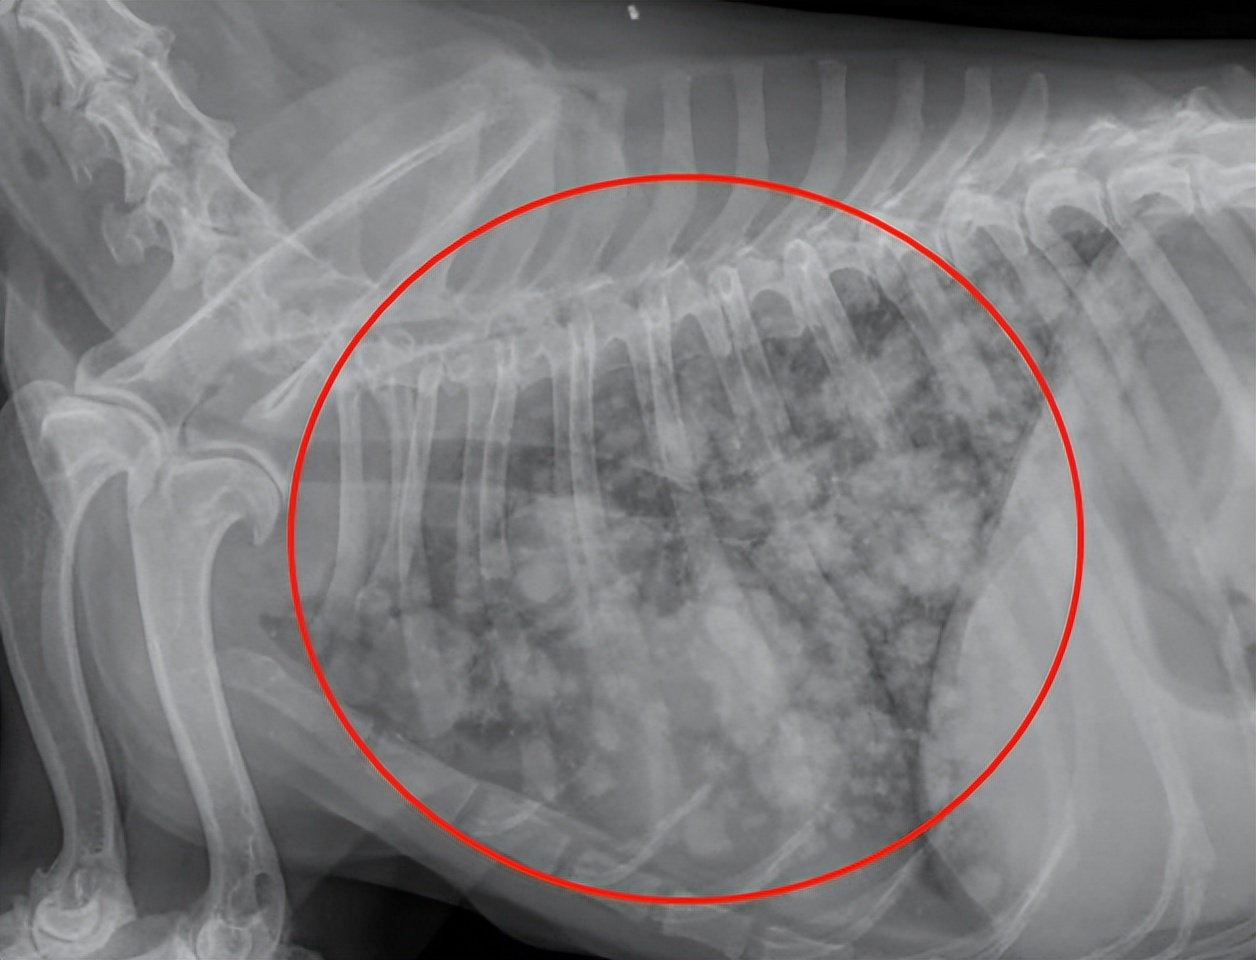

希望每个主人带狗狗检查时不要呈现这样的照片!下面这张图就是乳腺癌肺部转移X光照片。

而乳腺肿瘤一旦恶化,就会使得皮肤裂开,肿瘤内部出现破裂。只要没有给做切除乳腺癌的手术,那么生长得特快的肿瘤就很有可能会出现破裂,甚至有些狗狗总是去舔乳房周围的皮肤的话还会加快破裂的速度。肿瘤通常扩散到局部淋巴结和肺部。